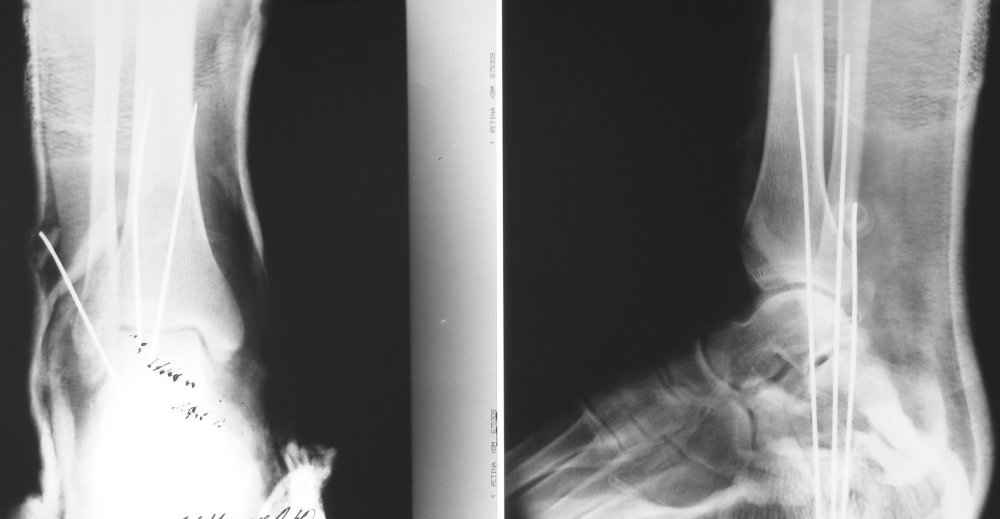

На лечении находится пациент 35 лет. Травма в сентябре 2008 г.- открытый вывих таранной кости

В день травмы ПХО, вправление вывиха, трансартикулярная фиксация. Рана зажила первично. С января нагрузка на конечность. С конца апреля- болевой синдром. На рентгенограммах и КТ признаки ас. некроза таранной кости, артроз подтаранного и голеностопного суставов.

У больного тотальный ас. некрох блока таранной кости, заинтересованы голеностопный и подтараный суставы. Эндопротезирование маловероятно на некротизированную кость. Изолированный подтаранный артродез таран не спасет.При артродезе всю некротизированную кость придется убрать.А далее замещение либо за счет большеберцовой кости, или удлинение на регенерате.